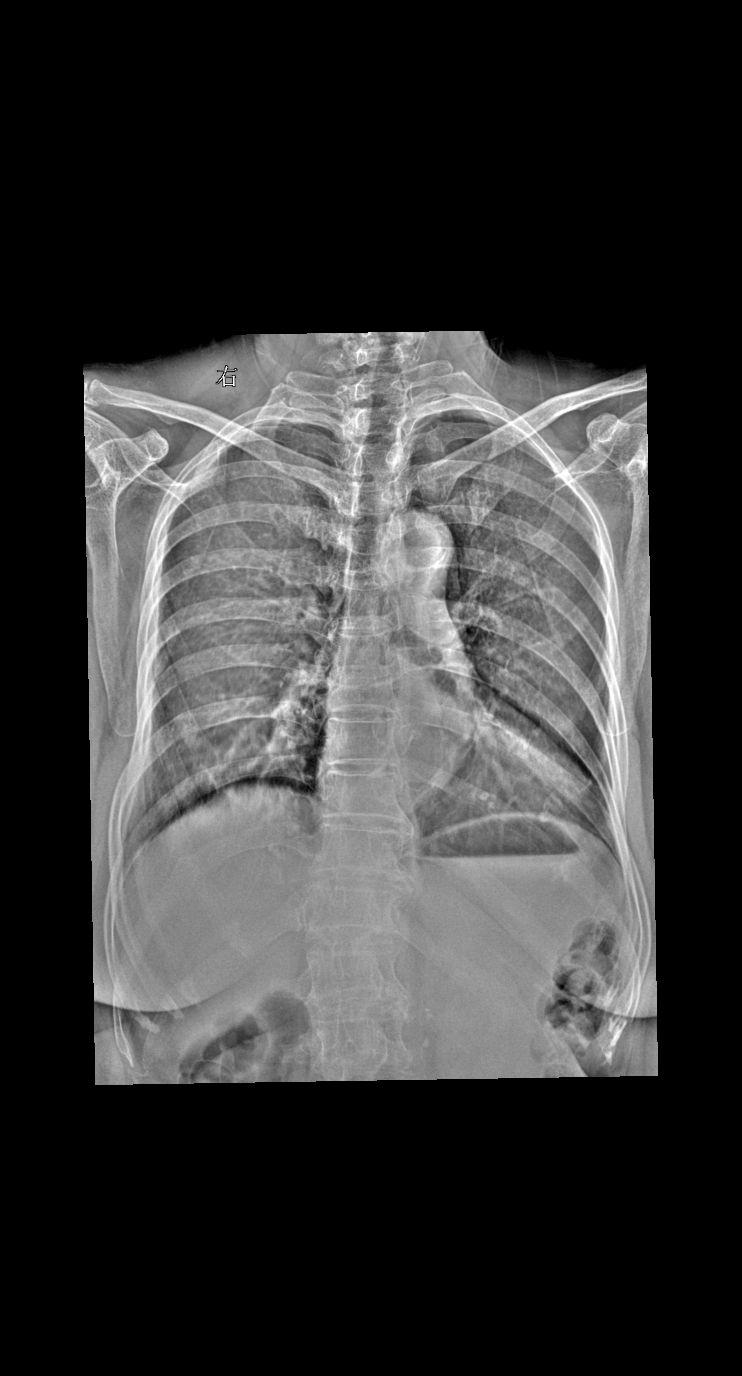

男 45外伤 胸廓正斜位

2025-11-09 19:06